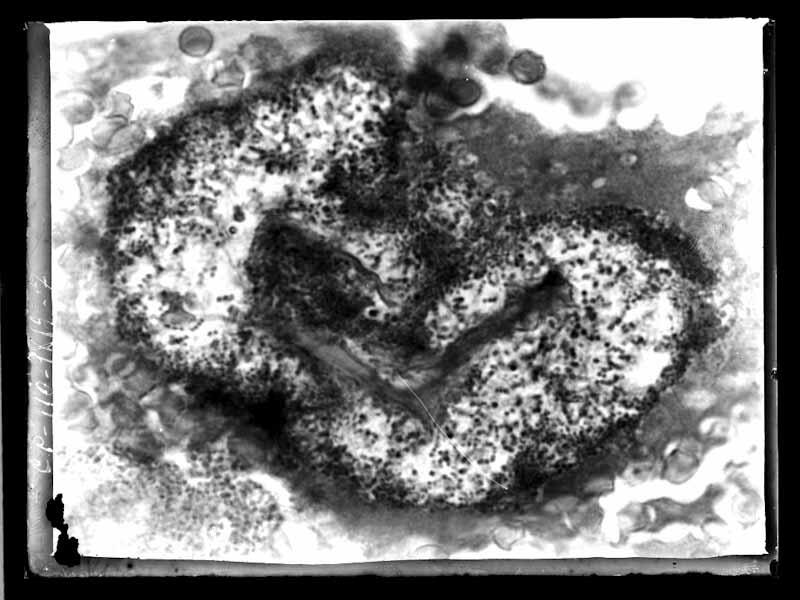

Fotomicrografia

Documentos iconográficos: 1 item (negativo de vidro p&b 9x12 cm)

Notação anterior: IOC-V-III-3570